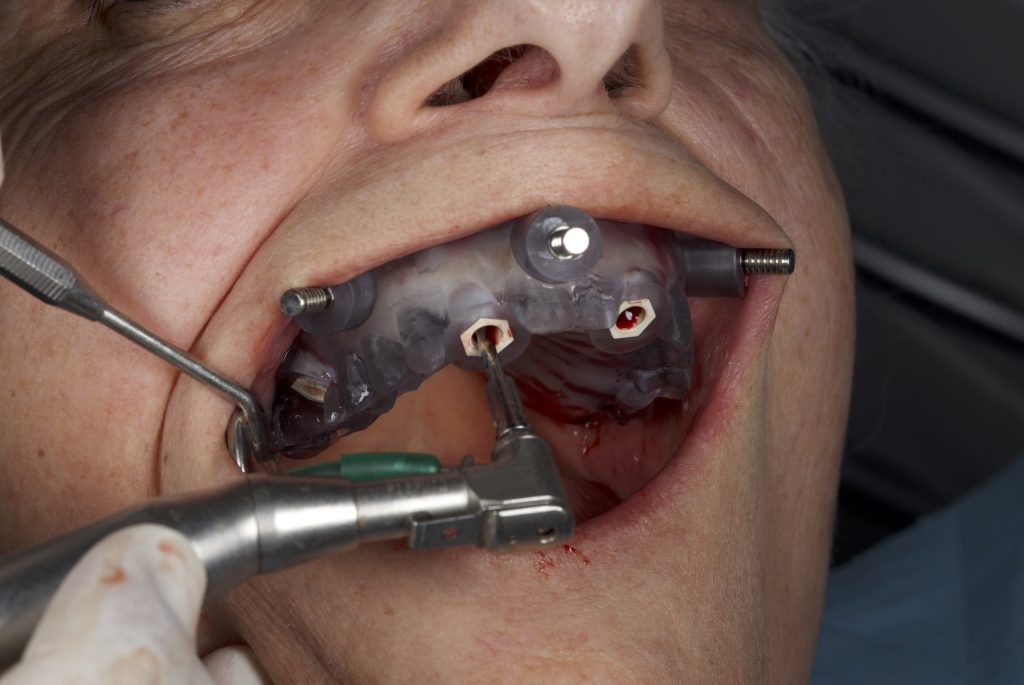

Previa anestesia locale con articaina 1:100.000, è stata fissata la dima guidata con frese di preparazione per i tre pin di fissaggio. Quindi, seguendo in sequenza le frese così come indicato per ogni sito implantare, sono stati inseriti i sei impianti mono-componente con MUA integrato B&B Dental con un torque d’inserzione di 35 N/cm. È stata eseguita una ops di controllo (Figure 8-13).